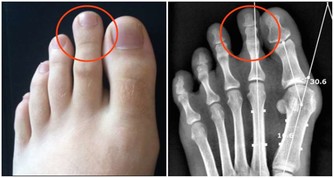

家住南京的張女士因為大腿內側疼和腳趾疼到南京市鼓樓醫院就診。她向醫生反映了一個細節,自己穿鞋子一直很費,一雙皮鞋穿3個月,底就被磨歪了,要打鞋掌。

骨科醫生的判斷「估計是髖關節出了問題。」CT掃描的結果證實了,張女士患有髖關節發育不良,長期拖著腿走路,所以鞋子一側磨損特別嚴重。林醫生表示,如果這位女士早些發現自己鞋子磨損得如此嚴重,早來就診,就不會發展到這麼嚴重。

正常人步行,呈輕度外八字形,鞋跟都會有或多或少的磨損,磨損位置集中於後跟外側,且對稱。通常情況下,如果新買的鞋子,半年磨掉20%以內,一般視為正常的。如果3個月內就磨損掉20%~30%,就不是走路姿勢的問題了,基本上可以判斷是身體出了問題。常見的原因,有髖關節疾病,像先天性髖關節半脫位,髖關節發育不良,脊柱側彎等。